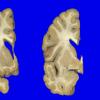

1A1 NCL (Case 1) gross 4

1A4 NCL (Case 1) gross 6